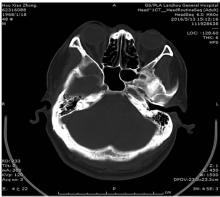

大灶性骨髓瘤是一种非常罕见的浆细胞瘤,目前对其生物学行为认识有限,易误诊为经典多发性骨髓瘤及其他髓外浆细胞瘤。现报道1例大灶性骨髓瘤的临床诊治经过,并对其临床特点及鉴别诊断进行探讨。